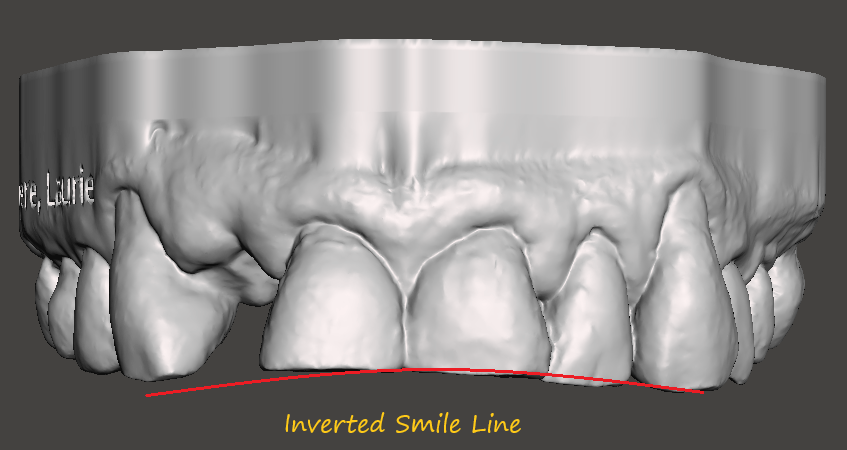

Worn or mal (bad) occlusion

Centrals, laterals and canine all worn flat by bruxism. The anterior teeth are either flat and in more severe cases presents with a an inverted smile line